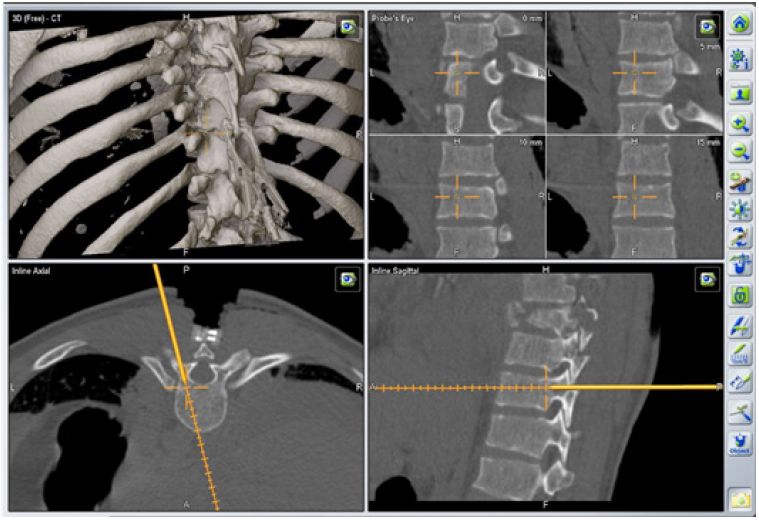

The patient undergone a surgery based on a hybrid minimal invasive approach using an intraoperative 3D CT-scan navigation system and percutaneous pedicle-screwing method. We performed a posterior thoracic spine fixation from Th2 to Th10. The patient was placed in a prone position on a mobile, radiolucent, carbon fiber operating table connected to the Airo ring (Figure 2A). A fluoroscopy was used to check the spinal alignment and to determine the vertebral levels to be instrumented. A medial posterior skin incision was performed from Th1 to Th11 down to the muscular fascia. At this stage, a navigated reference marker clamp was firmly placed with minimal muscle dissection on the spinous process of Th9, which was the closest intact bony structure adjacent to the fractured levels [10] (Figure 2B). A first intraoperative CT-scan acquisition was performed, assessing a good kyphosis correction (Figure 3). The acquired datas were processed thanks to the intraoperative image-guidance system. A series of trans-pedicular channel was performed from Th10 to Th7, based on the 3D navigated CT-scan with a navigated standard Jamshidi needle (Figure 4) K-wires were inserted into the pedicles before insertion of cannulated screws. Additional lateral fluoroscopy was performed at the end of each screw placement in order to verify the screwing accuracy and the absence of bone displacement [12]. A second series of pedicular screwing was then realized using the same procedure under the control of a second CT-scan with a Th4 reference marker clamp. Two 24cm slightly bent titanium rods were placed in a strictly minimal invasive way to connect the screws. A vertebral distraction was applied to the vertebral body of Th8 to restore correct vertebral height and complete the procedure. Further decompressive laminectomy was unnecessary, as the MRI did not highlight any spinal cord compression.

Figure 4: Intraoperative 3D-navigated screw placement trajectory.